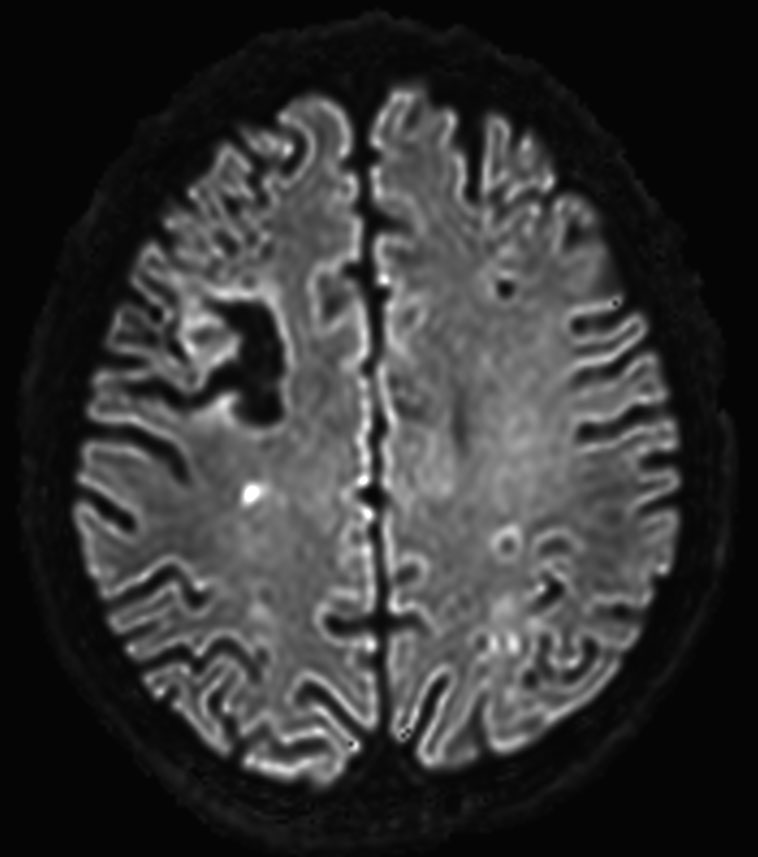

DWI b2000 (computed)

-

DWI b3000 (computed)